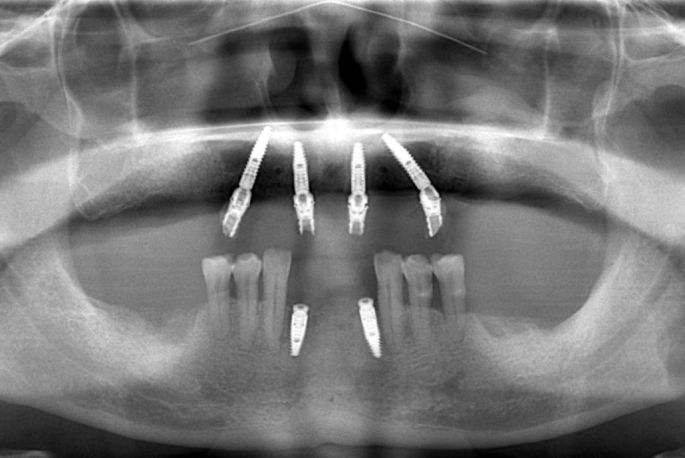

An immediate impression was obtained using a stabilization splint, and the occlusal relationship following surgery was recorded (Fig. 3a). Subsequently, computer-aided design/computer-aided manufacturing (CAD/CAM) resin prostheses were fabricated (Fig. 3b). The prosthetic length was determined based on the distal implant location to prevent cantilever and restore 6 to 8 teeth. The immediate restoration was completed within one week postoperatively (Fig. 3c). To ensure proper placement of the prosthesis, panoramic imaging was performed (Fig. 4). Patients were advised to consume soft foods and utilize an irrigator and interproximal brushes to maintain oral hygiene.

Panoramic imaging of immediate restoration.